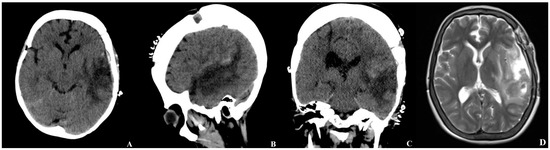

During her ward stay, the patient developed diabetes insipidus, which was well-controlled with desmopressin therapy. Control CT and MRI obtained on postoperative day 7 demonstrated resolution of the midline shift and a decrease in cerebral edema compared with the preoperative findings (Figure 5). Histopathological evaluation revealed no evidence of vascular malformations.

Figure 5. Brain CT and MRI obtained on the seventh postoperative day ((A) axial, (B) sagittal, (C) coronal view, (D) axial T2-weighted image). The postoperative CT demonstrates resolution of the previously observed midline shift and a marked decrease in perilesional cerebral edema. No new hemorrhage or ischemic changes are evident. The corresponding MRI sequences confirm a reduction in the mass effect, an improvement in ventricular compression, and postoperative changes consistent with hematoma evacuation.